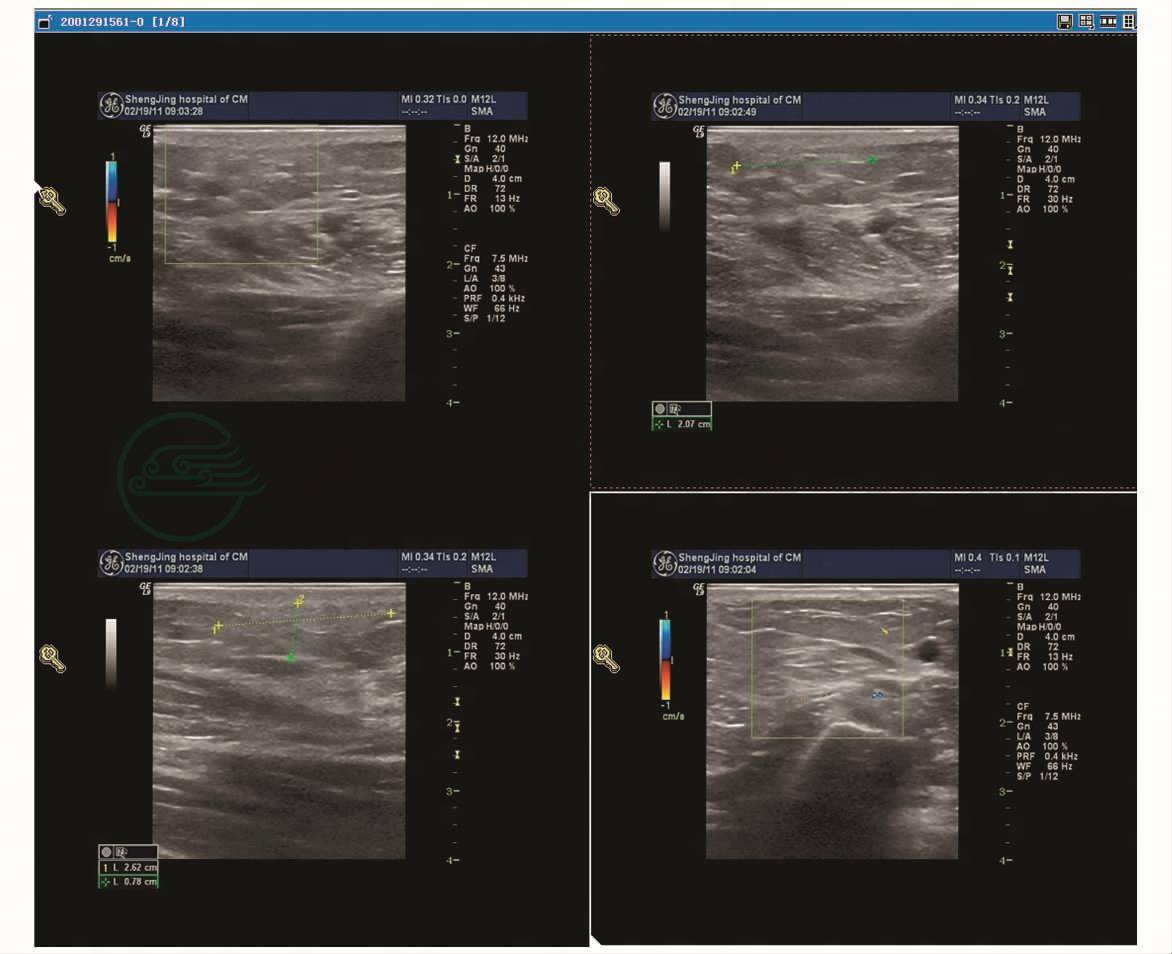

乳腺彩超示右乳囊实混合性包块,部分呈乳头样(图2);实性部分为不均质中等回声,CDFI探及血流信号(图3),但不易探及血流流速曲线;囊性部分见密集点状回声,可缓慢移动;双腋下未探及异常肿大淋巴结。

图2 术前超声图像

图3 术前超声图像